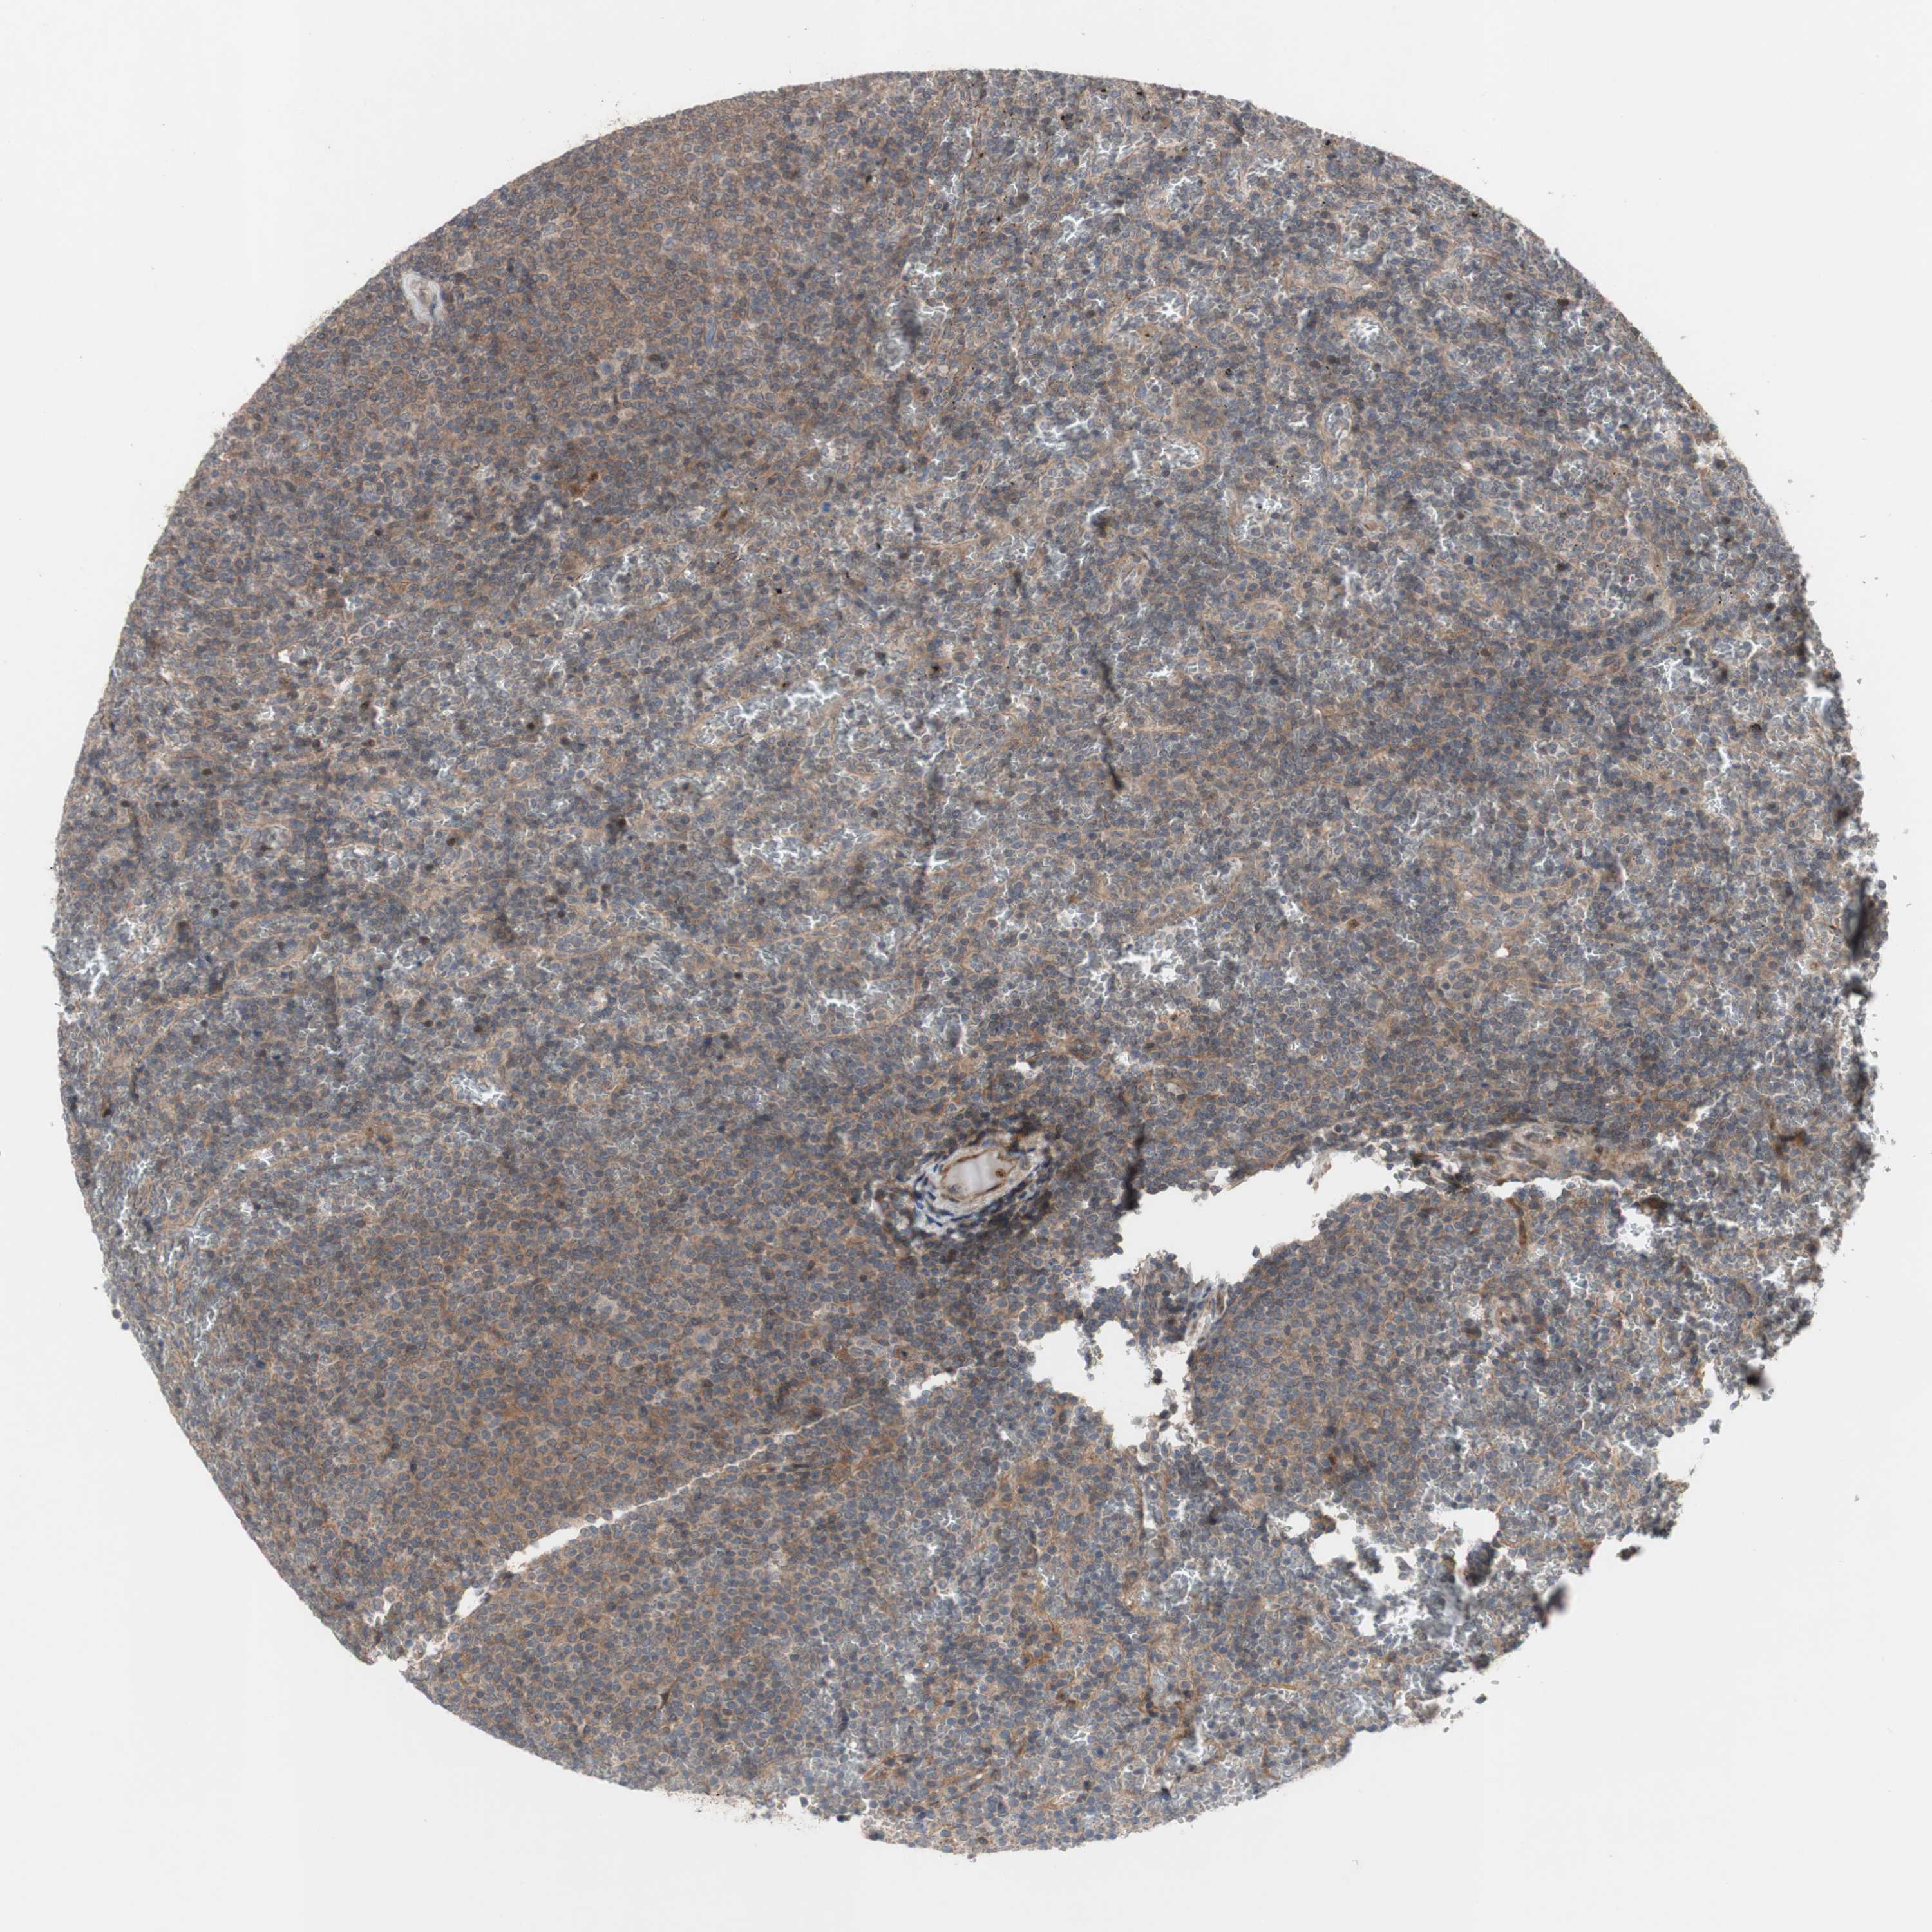

CANCER LYMPHOMA Show tissue menu

LYMPHOMA - Protein expressioni

A mouse-over function shows sample information and annotation data. Click on an image to view it in a full screen mode. Samples can be filtered based on level of antibody staining by selecting one or several of the following categories: high, medium, low and not detected. The assay and annotation is described here.

Each image is clickable and will lead to virtual microscopy that enables deeper exploration of all samples and also displays staining intensity scores, fraction scores and subcellular localization as well as patient and tissue information for each sample.

Antibody HPA009291

Staining

High

Medium

Low

Not detected

Intensity

Strong

Moderate

Weak

Negative

Quantity

>75%

75%-25%

<25%

None

Location

Nuclear

Cytoplasmic/membranous

Cytoplasmic/membranous,nuclear

Hodgkin's disease, NOS

Malignant lymphoma, non-Hodgkin's type, Low grade

Malignant lymphoma, non-Hodgkin's type, High grade